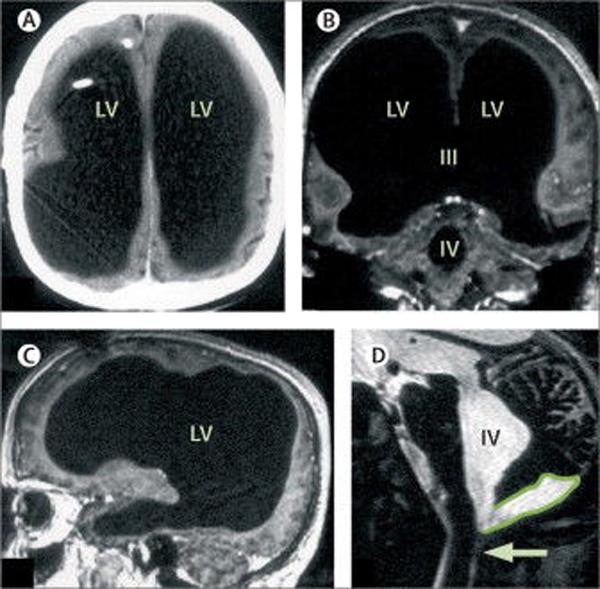

Các bác sĩ tại bệnh viện đã vô cùng kinh ngạc khi xem phim chụp não của người này bởi chỉ có một chút não nằm trong hộp sọ, còn lại toàn bộ là chất lỏng, chất xám và chất trắng đều không thấy.

Phim chụp não bộ "trống không" của người đàn ông 44 tuổi vẫn sống khỏe, lấy vợ và sinh con.